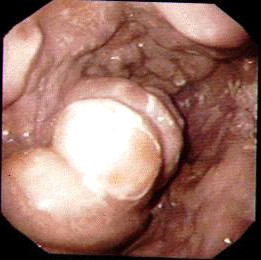

אנמנזה טובה ובדיקה פיזיקלית יכולות לספק אינפורמציה רבה על שאלות אלה. פירוט של האנמנזה והממצאים בבדיקה הפיזיקלית כפי שצוינו בתחילת פרק זה הם המרכיבים העיקריים באבחנה. לכל חולה כזה יש לבצע בדיקות דם מקיפות, כולל תפקודי כבד, תפקודי קרישה ותפקודי כליות. לאחר הערכה ראשונית וטיפול במצב החד, יש לבצע אנדוסקופיה על מנת לברר מה מקור הדימום ולראות האם לחולה יש דליות מדממות (תמונה 2.10). אם לחולה יש דליות מדממות אפשר להזריק לתוכן חומר מטרש ועל-ידי כך לעצור את הדימום. אפשר גם לבצע בליעת בריום על מנת להדגים דליות, כיבים פפטים, בקעים בסרעפת וכו'. ל- 52% מהחולים בעלי דליות יש גם כיבים פפטים. רק ב- 50% מהחולים בעלי דליות הוושט ניתן לראות דליות בבליעת בריום ולכן העדיפות המוחלטת של האזופגוסקופיה לבירור דליות.